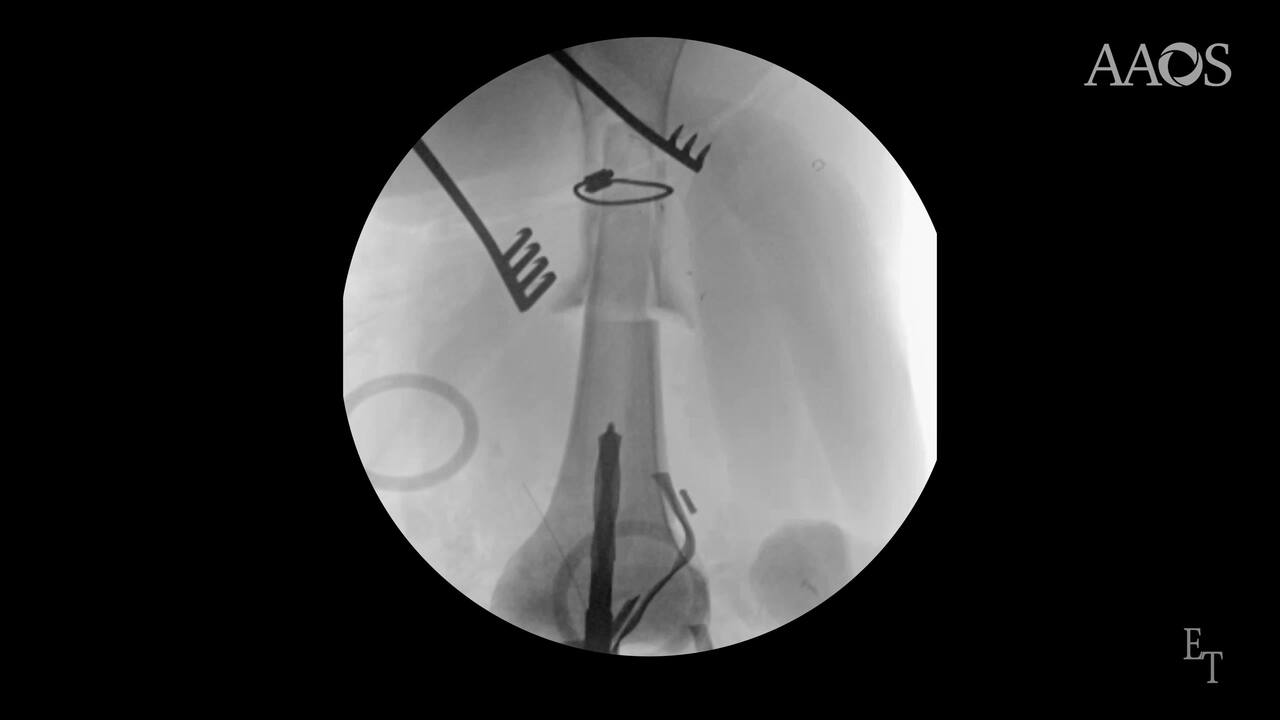

Results: An incision was made through the previous anteromedial incision. Scar tissue surrounding the implant were peeled away and flaps were developed. Once the implant was exposed, the fusion component at the knee joint level was disengaged. The femoral component and tibial components were removed using a burr. A proximal tibial allograft was measured and cut to size to fit the femoral canal. The femoral canal was enlarged using a burr and a braided cable was prophylactically placed proximally around the femur. The tibial allograft was then telescoped into the femur. The femur with the tibial allograft were reamed to accommodate the distal femoral stem. Next, the metaphysis was reamed to accommodate a cone and a trial cone was placed.

Trial components are placed and traction was placed on the extremity to assess overall length of the construct. Once satisfied, the tibial and femoral components was assembled and cemented into placed. The hinge component was then linked and range of motion was assessed. A limited contact compression plate was then cut to the appropriate length and placed along the telescoping portion of the construct and secured with unicortical and bicortical screws. The wound was thoroughly irrigated with a betadine solution, and the wound was closed in a layered fashion.